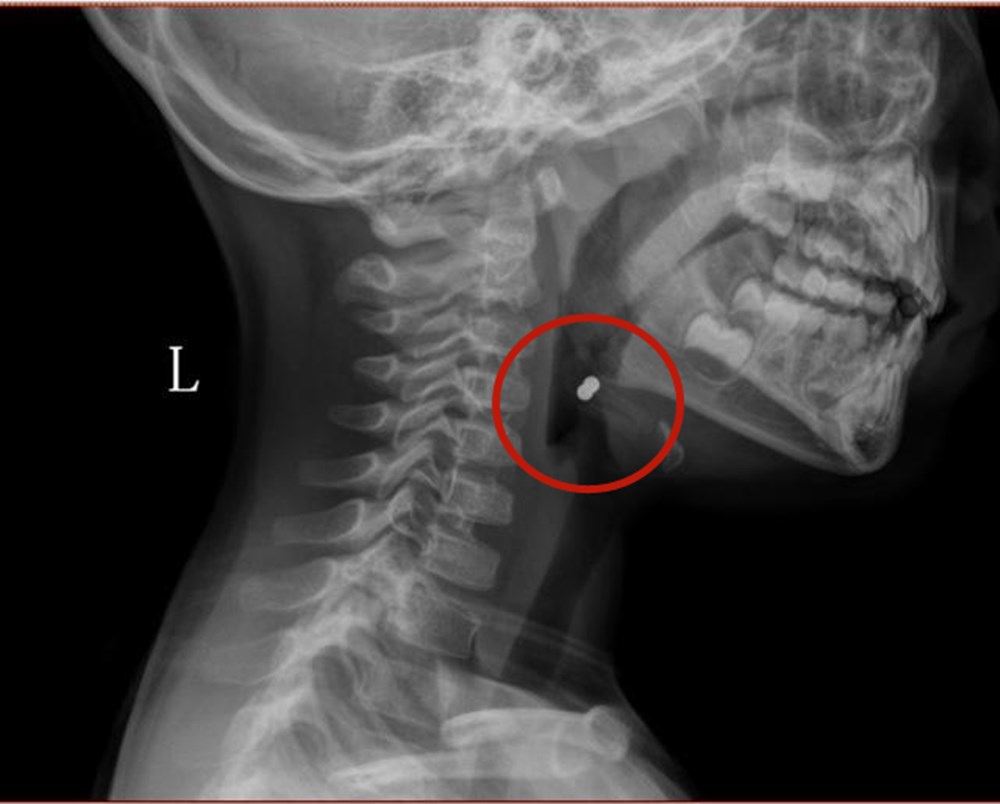

4月3日,《齐鲁晚报》报道,一名3岁小娃误吞巴克球,两个磁力球相互吸引悬浮在咽喉部,随时会掉落,还吞进肚子里8颗,所幸手术顺利。

小孩子好奇心重,特别是处于口腔敏感期的小宝宝,总是抓到什么吃什么,对于这种外形和糖豆很接近的磁力球,更是毫无抵抗力,一旦误吞,磁珠有可能会阻塞食管,造成窒息。

而又因为磁珠特殊的性质,在进入胃肠后会相互吸引,紧贴在一起的部位会出现血供应不足,引起消化道破裂穿孔,威胁生命。

如果孩子够幸运的话,单颗巴克球可能会自行排出,通常会通过内镜取出。

而如果吞食了多颗,巴克球在肠胃中“你追我赶”,需要紧急通过开腹手术来移除,还很可能对儿童的消化道造成不可逆的伤害。